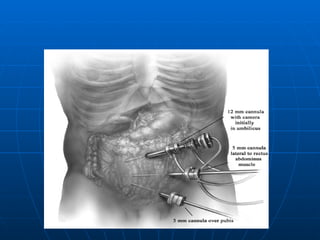

TRATAMIENTO LAPAROSCOPICO Excelente Iluminación y exposición del campo operatorio Disminución de Complicaciones Mayor costo (equipos- anestesia general) Mayor tiempo Operatorio ( 3 Trócares umbilical,suprapúbico (10mm y fosa iliaca izquierda 5mm). En todos los grupos cuando el Apéndice es normal  no se extrae (no así en las convencionales)

TRATAMIENTO LAPAROSCOPICO ExcelenteIluminación y exposición del campo operatorio Disminución de Complicaciones Mayor costo (equipos- anestesia general) Mayor tiempo Operatorio ( 3 Trócares umbilical,suprapúbico (10mm y fosa iliaca izquierda 5mm). En todos los grupos cuando el Apéndice es normal no se extrae (no así en las convencionales)